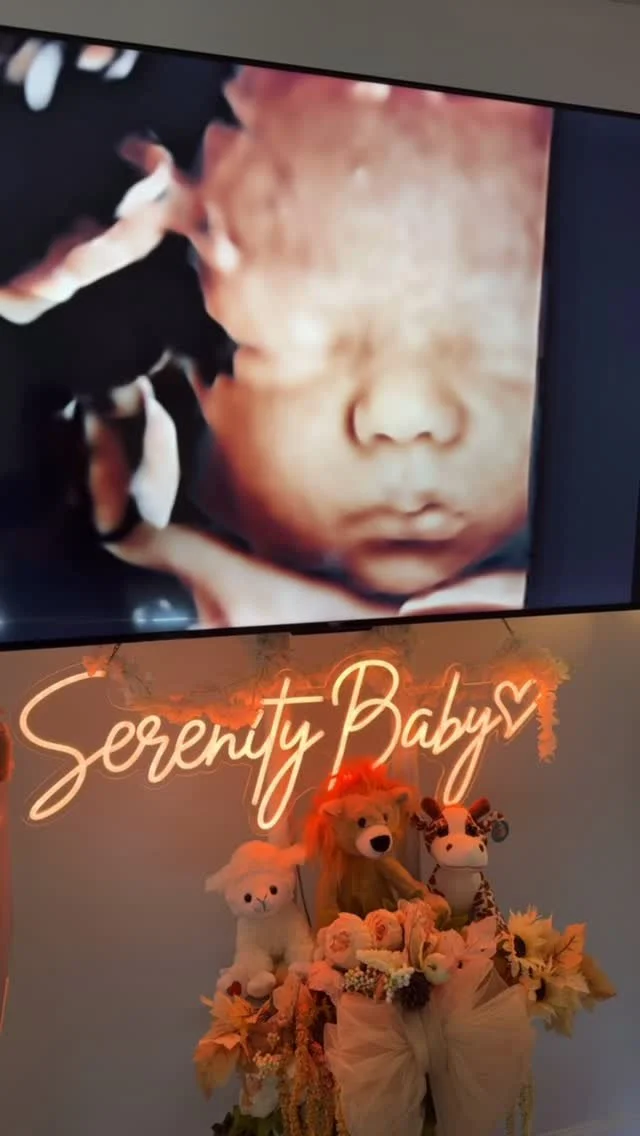

Serenity Imaging

“Where First Moments Become Forever Memories”

3D/4D/5D HD Live Ultrasound

3D/4D/5D baby ultrasound service. We are revolutionizing the way expecting parents can bond with their little ones even before they are born. These advanced ultrasound technologies provide a vivid and lifelike representation of the baby in the womb, capturing charming details that previously remained unseen.

With elective 3D ultrasounds, parents can now see the contours of their baby's face, tiny fingers, and delicate features with astonishing clarity.